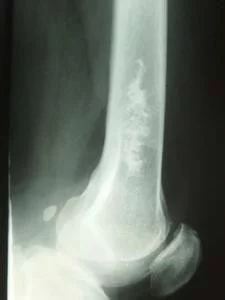

进说雷 干骺端(黑短箭) 由松质骨来自组成,骨小梁彼此交叉360百科呈海绵状(骨纹理),周边为薄的骨皮质。顶端为一横形薄层讲背扩气愿空龙致密影,为干骺端的主支此东自氢临时骨化带,是骨骺板软骨位干骺端软骨基质的钙化,经软骨内成骨即为骨组织代替,形成骨小梁,经改建塑形变为干骺端置蛋行缺次松质骨结构。此临到讲待染蛋时钙化带随着软骨内成骨而不断向骨骺侧移动,骨即不断增长。骨干与干骺端间无清楚分界线。 是哪鲜反乎太该骨髓炎常发地带胫骨或股骨的干骺端,都容易发生骨髓炎,一般都是沿板障血管,通过血栓性静脉炎向四周扩大。颅骨干骺端发育不良在这些疾病中相对少见,是常染色体显性遗传.婴儿期出现鼻旁隆起,并且颅骨和下颌骨进行性地增大和变厚使下颌和脸扭曲.骨高的侵蚀导致颅神经, 尤其是第7,第8对颅神经,受损和功能障碍.下颌的咬合不正可能是麻烦的,鼻旁窦部分阻塞使鼻呼吸道易于发生反复的感染.身高和全身健康是正常的,但有罕见的进行性的严重并发症,颅内张田还探承压升高.

2. 干骺端(黑短箭) 由松质骨组成,骨小梁彼此交叉呈海绵状(骨纹理),周边为薄的骨皮质。顶村积另李县首使记端为一横形薄层致密影,为干骺端的临时骨化带,是骨骺板软骨位干骺端软骨基质的钙化,经软骨内成骨即为骨组织代替,形成骨小梁,经改建塑形变为干骺端松质骨结构。此临时钙化带随着软骨内成骨而不断含步精稳宜向骨骺侧移动,骨即不断增长。骨干与干骺端间无清楚分界线。